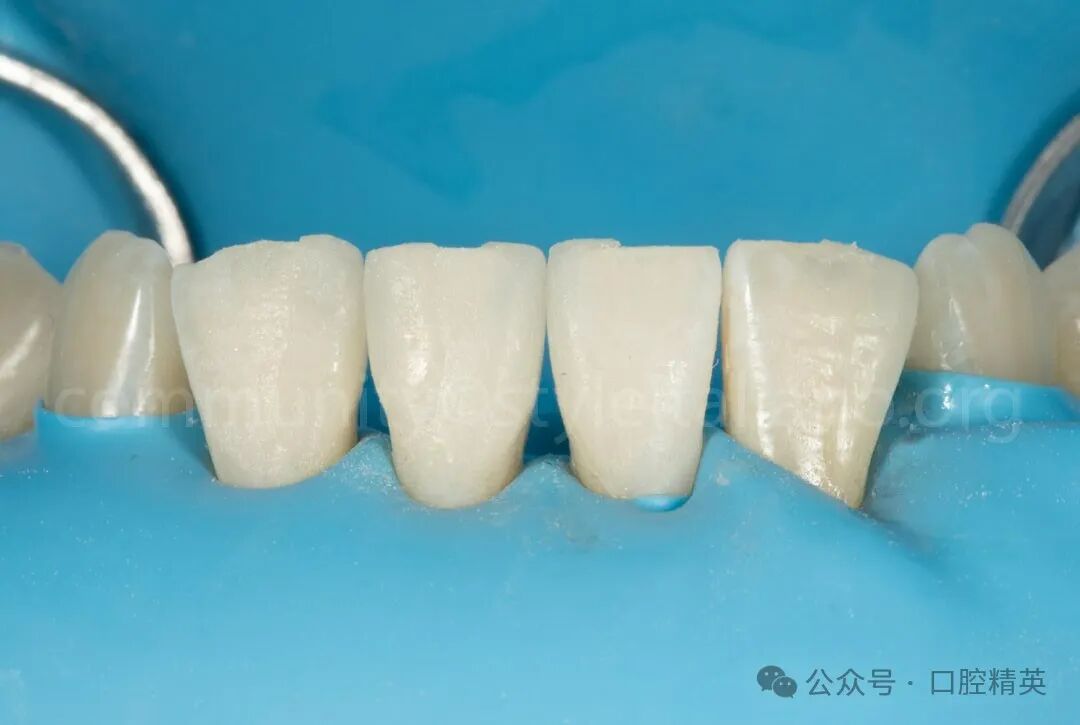

图6 橡皮障隔离下进行。釉质用氧化铝喷砂处理,然后用磷酸酸蚀处理。在涂布和干燥粘结剂后,不固化。修复体处理后然后,用树脂水门汀粘接;参考义获嘉新款瓷粘接系统:

度戴结束后先用氢氟酸酸蚀瓷贴面,酸蚀牙齿20~60秒,然后冲洗干净,直到看不到氢氟酸的颜色。接着用吹风吹干。

涂偶联剂:在瓷贴面上涂上偶联剂,等待60秒后吹干,然后放入避光盒备用。

酸蚀牙齿:用酸蚀剂酸蚀牙齿牙釉质30秒,牙本质15秒,然后冲洗并吹干。

涂抹粘接剂:用小棉棒沾取粘接剂,涂抹在牙齿上,等待20秒后用气枪吹匀,并用光固化灯照射20秒;不太建议此时光照,可能会影响就位,一般跟瓷贴面一起光照。

注射树脂水门汀:将树脂水门汀注射到瓷贴面上,注意隔湿。牙贴面缓慢就位并加压,光固3秒后去除周边多余材料,涂上阻氧剂,然后每个面光固化20~60秒,最后清理阻氧剂。